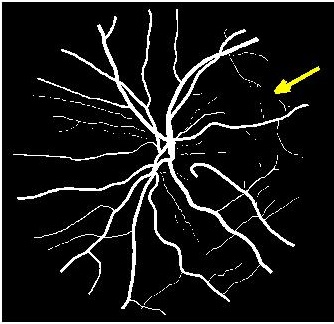

Figure 3 shows super resolution results for retinal fundus images. The image has been downsampled by a factor of each along rows and columns, and the original image is obtained using different methods. shows better reconstruction results (Fig. 3 (d) )than most competing methods. However the reconstruction is a bit blurry for small retinal vessels using as indicated by the yellow arrow. This defect is overcome using the proposed architecture (Fig. 3 (c) ), thus justifying the use of progressive GANs over saliency maps for image super resolution.

Figure 4 (a) shows an example retinal image followed by its ground truth manual segmentation in Figure 4 (b). Figure 4 (c) shows segmentation result for scaling factor when using the original HR images to train the U-Net followed by the results when trained on the super resolved images generated by , (Figure 4 (d)), (Figure 4 (e)), (Figure 4 (f)), SR-RF (Figure 4 (g)), SSR (Figure 4 (h)) and (Figure 4 (i)). Obviously the results from provide results most similar to those of HR images. This is also validated by the quantitative results in Table 3. The areas where different methods are unable to obtain accurate segmentation are highlighted by yellow arrows. Due to poor quality of super resolved images most of the methods do not segment the finer vasculature structures, while SSR and SR-RF are unable to segment some of the major arteries. Importantly, our method performs much better than the low resolution image () which performs poorly due to low resolution.

![]() |

| (a) | (b) | (c) | (d) | (e) |

| (f) | (g) | (h) | (i) | (j) |